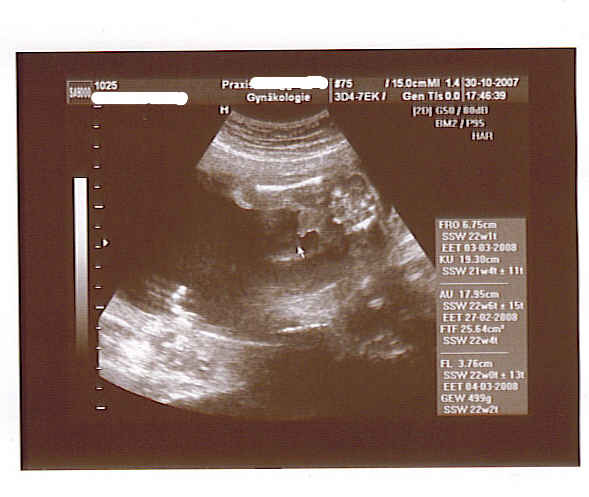

Ich darf morgen endlich wieder zu meiner Ärztin und bin schon super gespannt. Mittlerweile sieht man sogar ab und an von außen leichte Beulen und auch mein Mann bekommt die Tritte, die jetzt auch eindeutig als Tritte zu erkennen sind, schon zu spüren. Ist ganz schön aktiv, unser Zwerg. Das kleine Reich ist nun auch bestellt und wird im Januar geliefert und einige Autos sind wir jetzt auch schon Probe gefahren - eine Entscheidung ist zwar noch nicht gefallen - aber wir sind mal wieder einen Schritt weiter